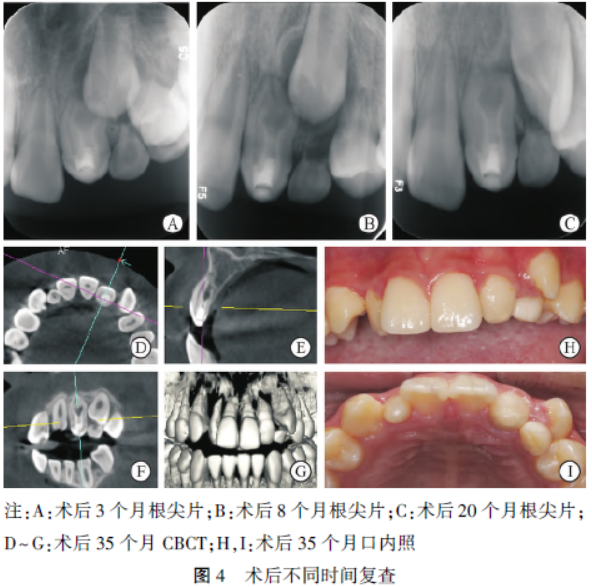

术后3 个月复查:22 充填体完好,叩诊(-),松动(-),牙龈无异常。根尖片示22 根尖周低密度影消失,23 牙胚较前向牙合方移动,63 牙根吸收2/3(图4A)。术后8 个月复查:22 无临床症状。根尖片示22 根尖周无明显异常,23 牙胚牙合向移动较前无明显变化,63 牙根吸收(图4B)。

术后20 个月复查:22 无临床症状。根尖片示22 根尖周无异常,牙根较前略有伸长,根管壁略有增厚,13 明显牙合向移动(图4C)。术后35 个月复查:22临床牙冠高度较初诊时增加,牙龈无异常,23 萌出,唇侧移位,63 滞留。CBCT 示22 牙根较术前明显伸长,根管壁增厚,根尖孔缩小(图4D~4I)。